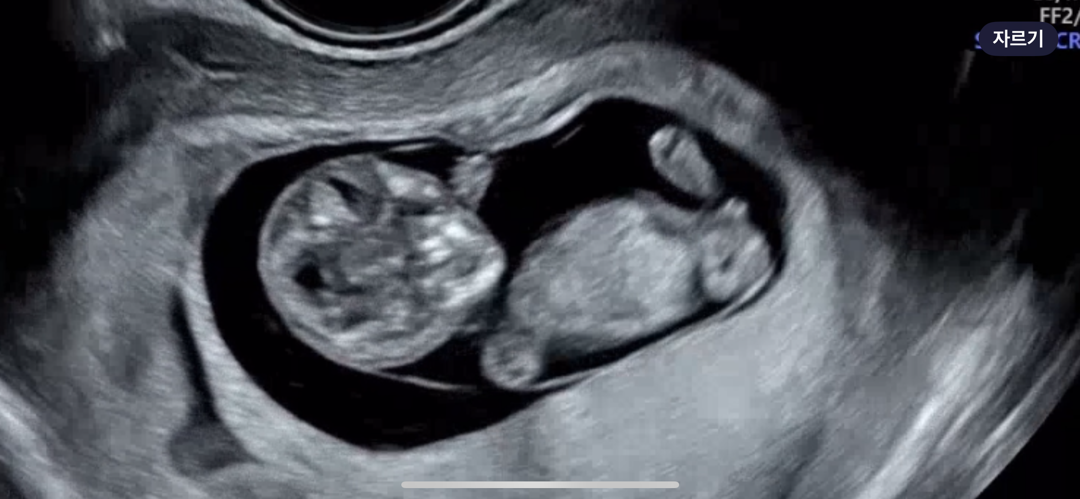

10주 4일차 초음파인데..

머리가 넘 큰거 같지 않나요?? 길이는 정상 주수 머리는 측정하니 12주가 나오더라구요 ㅠ 아이고 이와중에 다리사이로 보이는거 🌶️일까요?? 😂